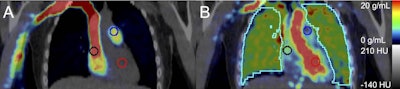

Participants underwent PET imaging with a radiotracer (fluorine-18 nitric oxide synthase [NOS]) that binds to a nitric oxide enzyme (iNOS) in pulmonary tissue. iNOS is a PET biomarker associated in prior studies with acute and chronic inflammatory diseases. A blood sample was also obtained to measure cytokine concentrations.

On the PET images, e-cigarette users showed greater binding activity between the tracer and iNOS than cigarette smokers (p = 0.03) and never smoked/vaped controls (p = 0.01), whereas binding in cigarette smokers did not differ from controls (p > 0.1), according to the results.

Moreover, F-18 iNOS binding in the lung imaging correlated significantly with blood concentrations of tumor necrosis factor alpha (TNF-a) (Spearman's rank correlation = 0.87, p = 0.05) in e-cigarette users. TNF-a is a potent inflammatory cytokine that responds to injured lung tissue.

"We find evidence that [e-cigarette] use causes a unique inflammatory response in the lungs, reflected by PET measures of iNOS expression and correlations with inflammatory biomarker concentrations," the authors wrote.